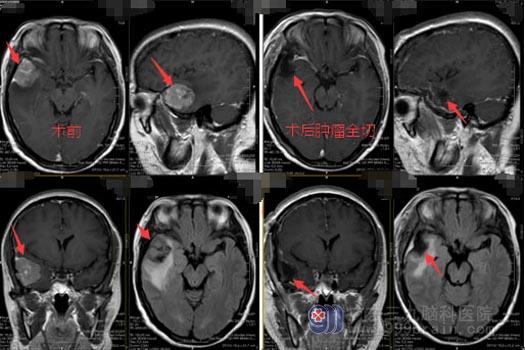

初步诊断“右侧颞叶占位”,入住广东三九脑科医院神经外五科。头颅MR提示:1.右侧颞部脑膜瘤可能, 2.脑白质少许变性灶;头颅CTA显示:右侧颞部占位病变,其内可见细小血管影,边缘细小血管参与供血,考虑血供丰富,脑膜瘤可能。

黄大姐及家人同意手术治疗。术中可见肿瘤侵犯右侧颞骨及硬脑膜,剪开硬脑膜后见灰白色肿瘤,质韧,分界清楚,位于侧裂血管颞侧,侵犯蛛网膜后破入颞叶组织,颞叶部分粘连;易于分离,血供一般,包膜不完整,起源于右侧颞部硬脑膜;分离与脑组织粘连的肿瘤,分块切除,创面止血,检查无活动性出血,脑组织搏动良好,手术过程顺利。

在神经外五科治疗团队的共同努力下肿瘤被顺利切除,术后黄大姐的生命体征平稳,意识清醒,四肢活动正常, 再过几天就可以出院回家了。